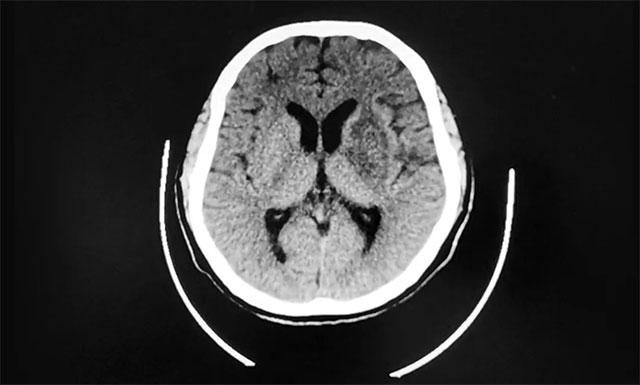

原本以为自己躲过了一劫,但是2020年6月初,小徐在家中再次倒下,紧急送往就近医院行头部 CT 显示左侧基底节、放射冠区、颞叶大面积脑梗塞,经过抢救病情平稳后转入上海蓝十字脑科医院进一步治疗。

▲ 大面积脑梗死